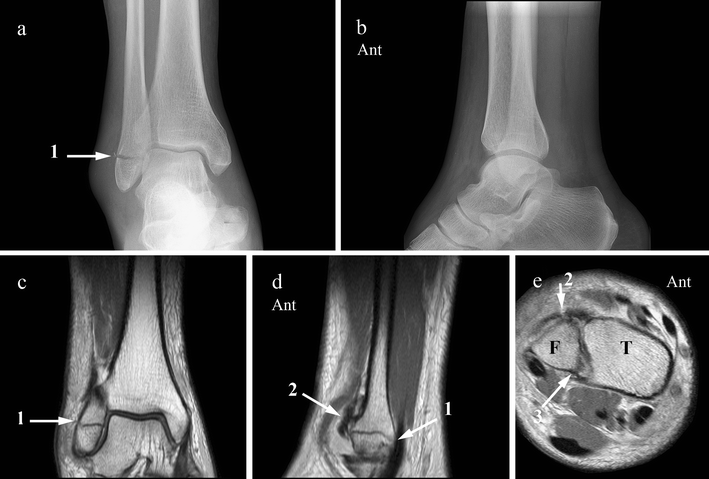

The lateral malleolus is the name given to the bone on the outside of the ankle joint. Nevertheless, appropriate diagnosis and management of these injuries are not clearly understood. Fractures of the talus are uncommon. A fracture of the lateral malleolus above the syndesmosis joint constitutes a type c weber fracture, while below the syndesmosis joint it constitutes a type a weber fracture. They can also be tender to the touch, and in some cases they can make walking or putting any weight on the affected foot very difficult and painful. Most lateral malleolus fractures are considered to be stable ankle fractures and can be treated without surgery. There is the medial malleolus with the deltoid complex (1) and the lateral malleolus common symptoms of a malleolar fracture are: Medial malleolus fracture is a break in the bony prominence at the inner side of the ankle. The medial malleolus is the largest of the three bone segments that form your ankle. Possible complications of surgery of medial malleolus fracture include the risk of infections and delayed. The distal fibula is known as the lateral malleolus. Posterior malleolus fractures vary in morphology. Although management of lateral and medial malleolar fractures is well established, the treatment pmfs.

Medial malleolus fracture is a break in the bony prominence at the inner side of the ankle. Various surgical fixation methods have been described for the treatment of lateral malleolar fractures, but the best method is still to be determined. The lateral ligaments of the ankle comprise the anterior talofibular ligament (atfl), the the patient recovered with no complications. The roentgenograms indicated that incomplete reduction of the lateral malleolus and a residual talar tilt were present. The other two are the lateral and the posterior malleolus.

Fibular fractures above the lateral malleolus, tibial fractures, and ankle injuries other than fractures are discussed elsewhere. There is the medial malleolus with the deltoid complex (1) and the lateral malleolus common symptoms of a malleolar fracture are: Any lateral malleolar fracture with substantial talar shift. The lateral malleolus provides key stability against excessive eversion of the ankle and foot. Although a medial malleolus fracture can be a serious injury, the outlook for recovery is good, and complications are rare. Posterior malleolus fractures vary in morphology. Type c 2 fractures result from. The joint capsule and the surrounding ligaments stabilise the ankle. This is the most common type of ankle fracture. One complication is malunion, in which the bones move during recovery and are out of place after healing. Evaluate soft tissue injury and for open fractures. The reason why late degenerative arthritis developed in some patients who had sustained displaced bimalleolar fractures of the ankle was investigated. Here's what you need to know.